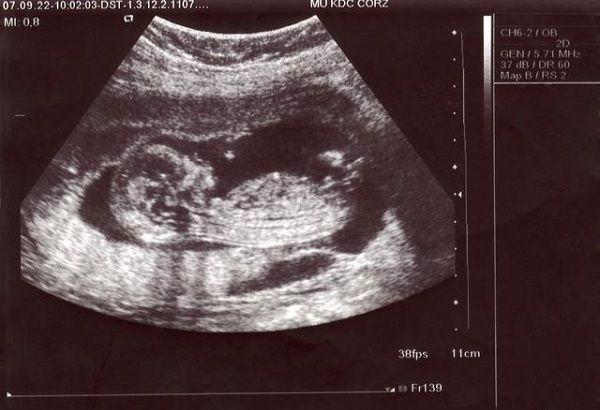

我定居国外,昨天去医院做了四维彩超,结果显示是女宝宝,我想知道这个检查准不准确,四维女孩会翻盘男孩吗?

四维彩超目前是国内最先进的超声检查,准确率是十分高的。并且四维彩超检查也确实能够对胎儿的性别进行判断,但还是在胎儿的性别判断结果上是不一定准确的。

四维彩超报告单

3、但是四维彩超通常都是怀孕24周左右进行检查的,孕周已经比较大了,所以出错的几率是相当小的,所以大多数情况下是不会出现翻盘的情况的。

总而言之,四维彩超是女孩翻盘为男孩的几率是不确定的,不要过于在意胎儿的性别。